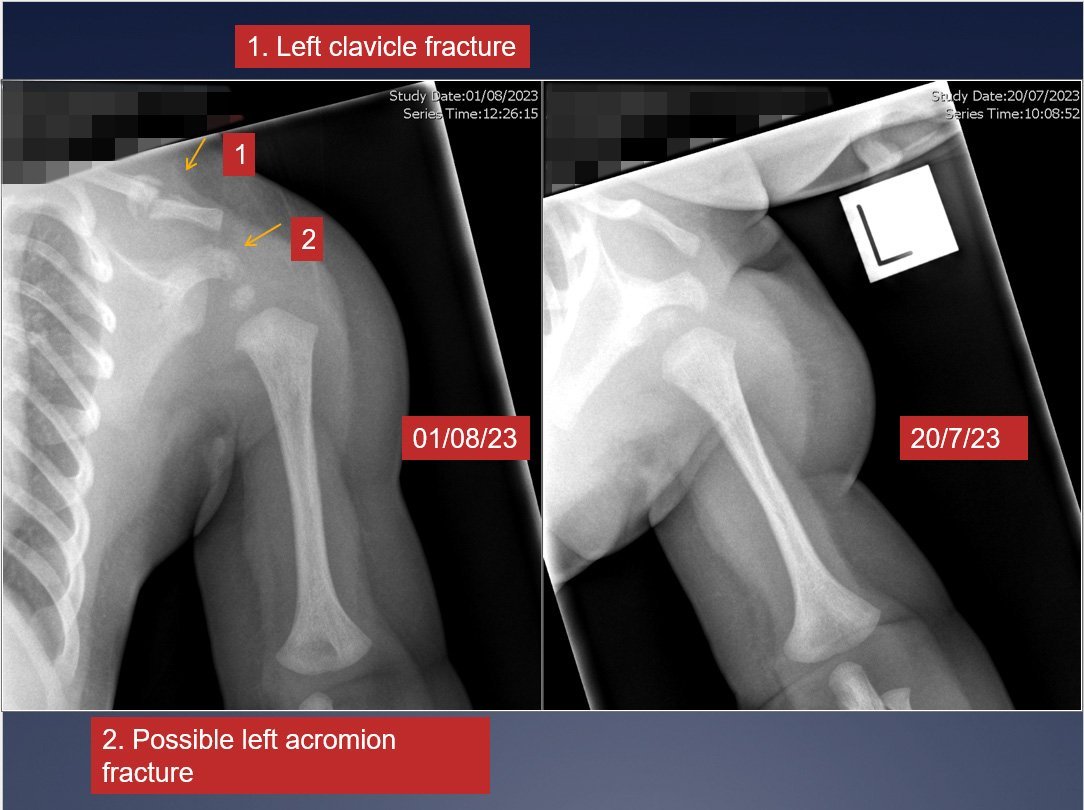

A baby brought to the hospital with no explanation for multiple rib fractures and a broken collarbone rang alarm bells for the paediatricians on the ground.

The fractures were "acute" and showed no signs of healing, meaning they had occurred in the past 10 days.

Paediatric radiologist Dr Russell Metcalfe said the injuries were "almost certainly the result of abusive trauma".

He believed the assault would have been a squeeze because of the pattern of the rib fractures.

Dr Benson said the baby’s vitamin-D deficiency had caused bone fragility and signs of this could be seen on X-ray.

"I am certain that his rib and clavicle fractures were birth related.

"When deficiencies are present ... healing is much delayed and the remodeling process can be delayed for months until sufficient minerals are available for normal bone repair and growth."